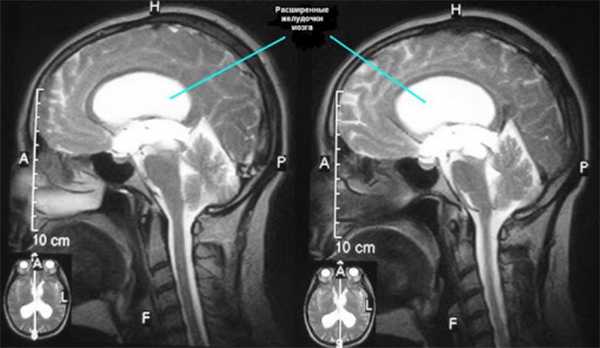

МРТ головного мозга. На МР-томограмме в сагиттальной плоскости отмечается расширение боковых желудочков мозга (линии), за счет повышенного содержания церебральной жидкости (ликвора).